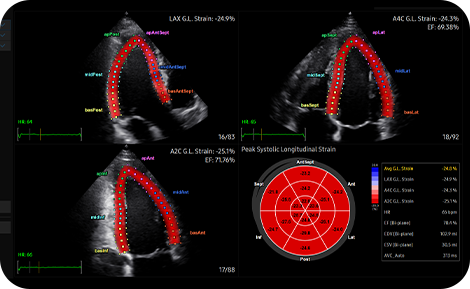

Quantify wall motion of the

left ventricle

Strain+ is a quantitative tool for measuring global and segmental wall motion of the left ventricle (LV). Three standard LV views and a Bull's Eye are displayed in a quad screen for easy and quick assessment of the LV function.

medical diagnostics : Strain+